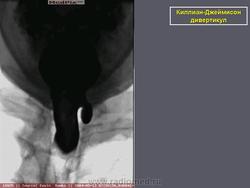

Киллиан – Джеймисон - дивертикул.

Приложения:

0.radiographics_logo.png0.rg_.337125153.fig15advustoronnyaya_killian-dzhemison_divertikulov_v_76-letney_zhenshchiny.gif0.rg_.337125153.fig15bdvustoronnyaya_killian-dzhemison_divertikulov_v_76-letney_zhenshchiny.gif